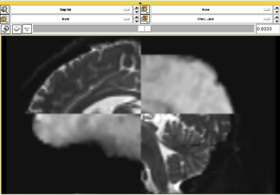

In this short tutorial, we will show how the Affine Registration module can be used to register two images from different subjects. The data is from the Oasis Brains project and the [http://www.loni.ucla.edu/Atlases/Atlas_Detail.jsp?atlas_id=6 ICBM. We will be registering the volumes icbm452_atlas_air12_sinc.hdr and OAS1_0001_MR1_mpr-1_anon.hdr. Be sure to load the volumes with the "Centered" option checked. Rotation is performed around the center, and a centered volume usually produces a more robust result.

Set the Fixed image to icbm452_atlas_air12_sinc.hdr and the moving image to OAS1_0001_MR1_mpr-1_anon.hdr. The default settings are sufficient to register these images

In this short tutorial, we will show how the Affine Registration module can be used to register two images from different subjects. The data is from the Oasis Brains project and the [http://www.loni.ucla.edu/Atlases/Atlas_Detail.jsp?atlas_id=6 ICBM. We will be registering the volumes icbm452_atlas_air12_sinc.hdr and OAS1_0001_MR1_mpr-1_anon.hdr. Be sure to load the volumes with the "Centered" option checked. Rotation is performed around the center, and a centered volume usually produces a more robust result.

Set the Fixed image to icbm452_atlas_air12_sinc.hdr and the moving image to OAS1_0001_MR1_mpr-1_anon.hdr. The default settings are sufficient to register these images